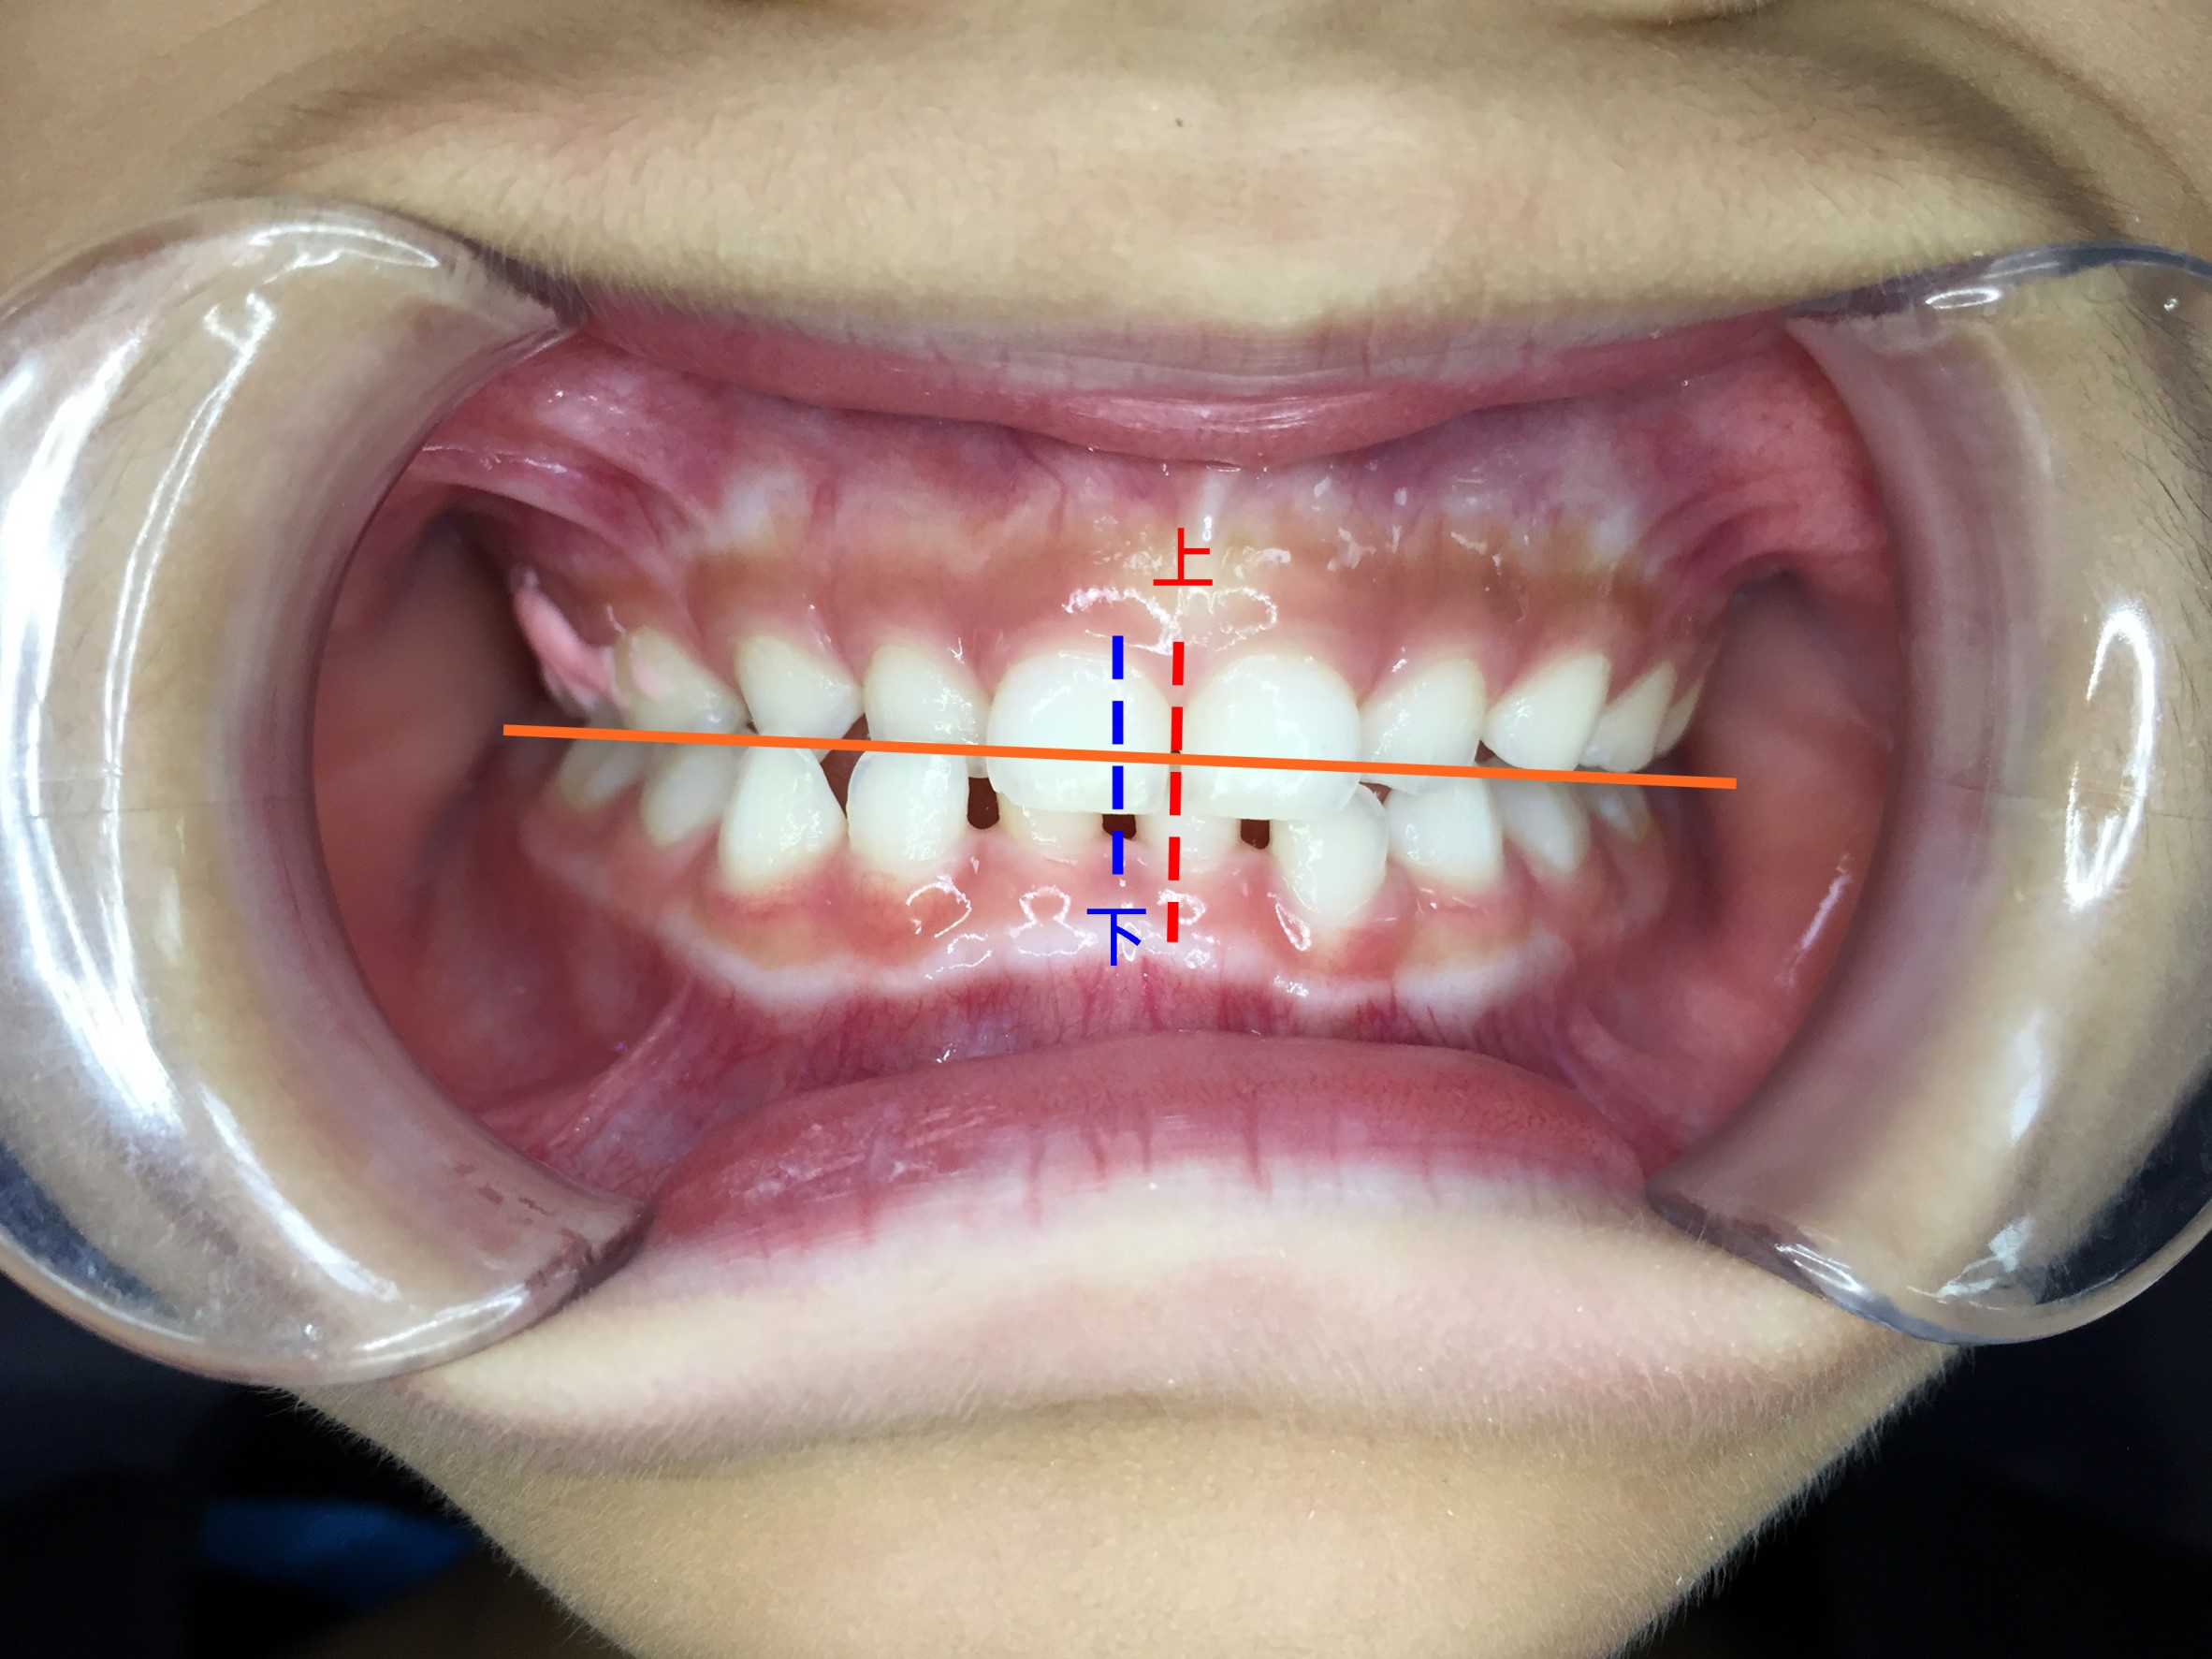

最常看到就是中線不齊,下巴歪。